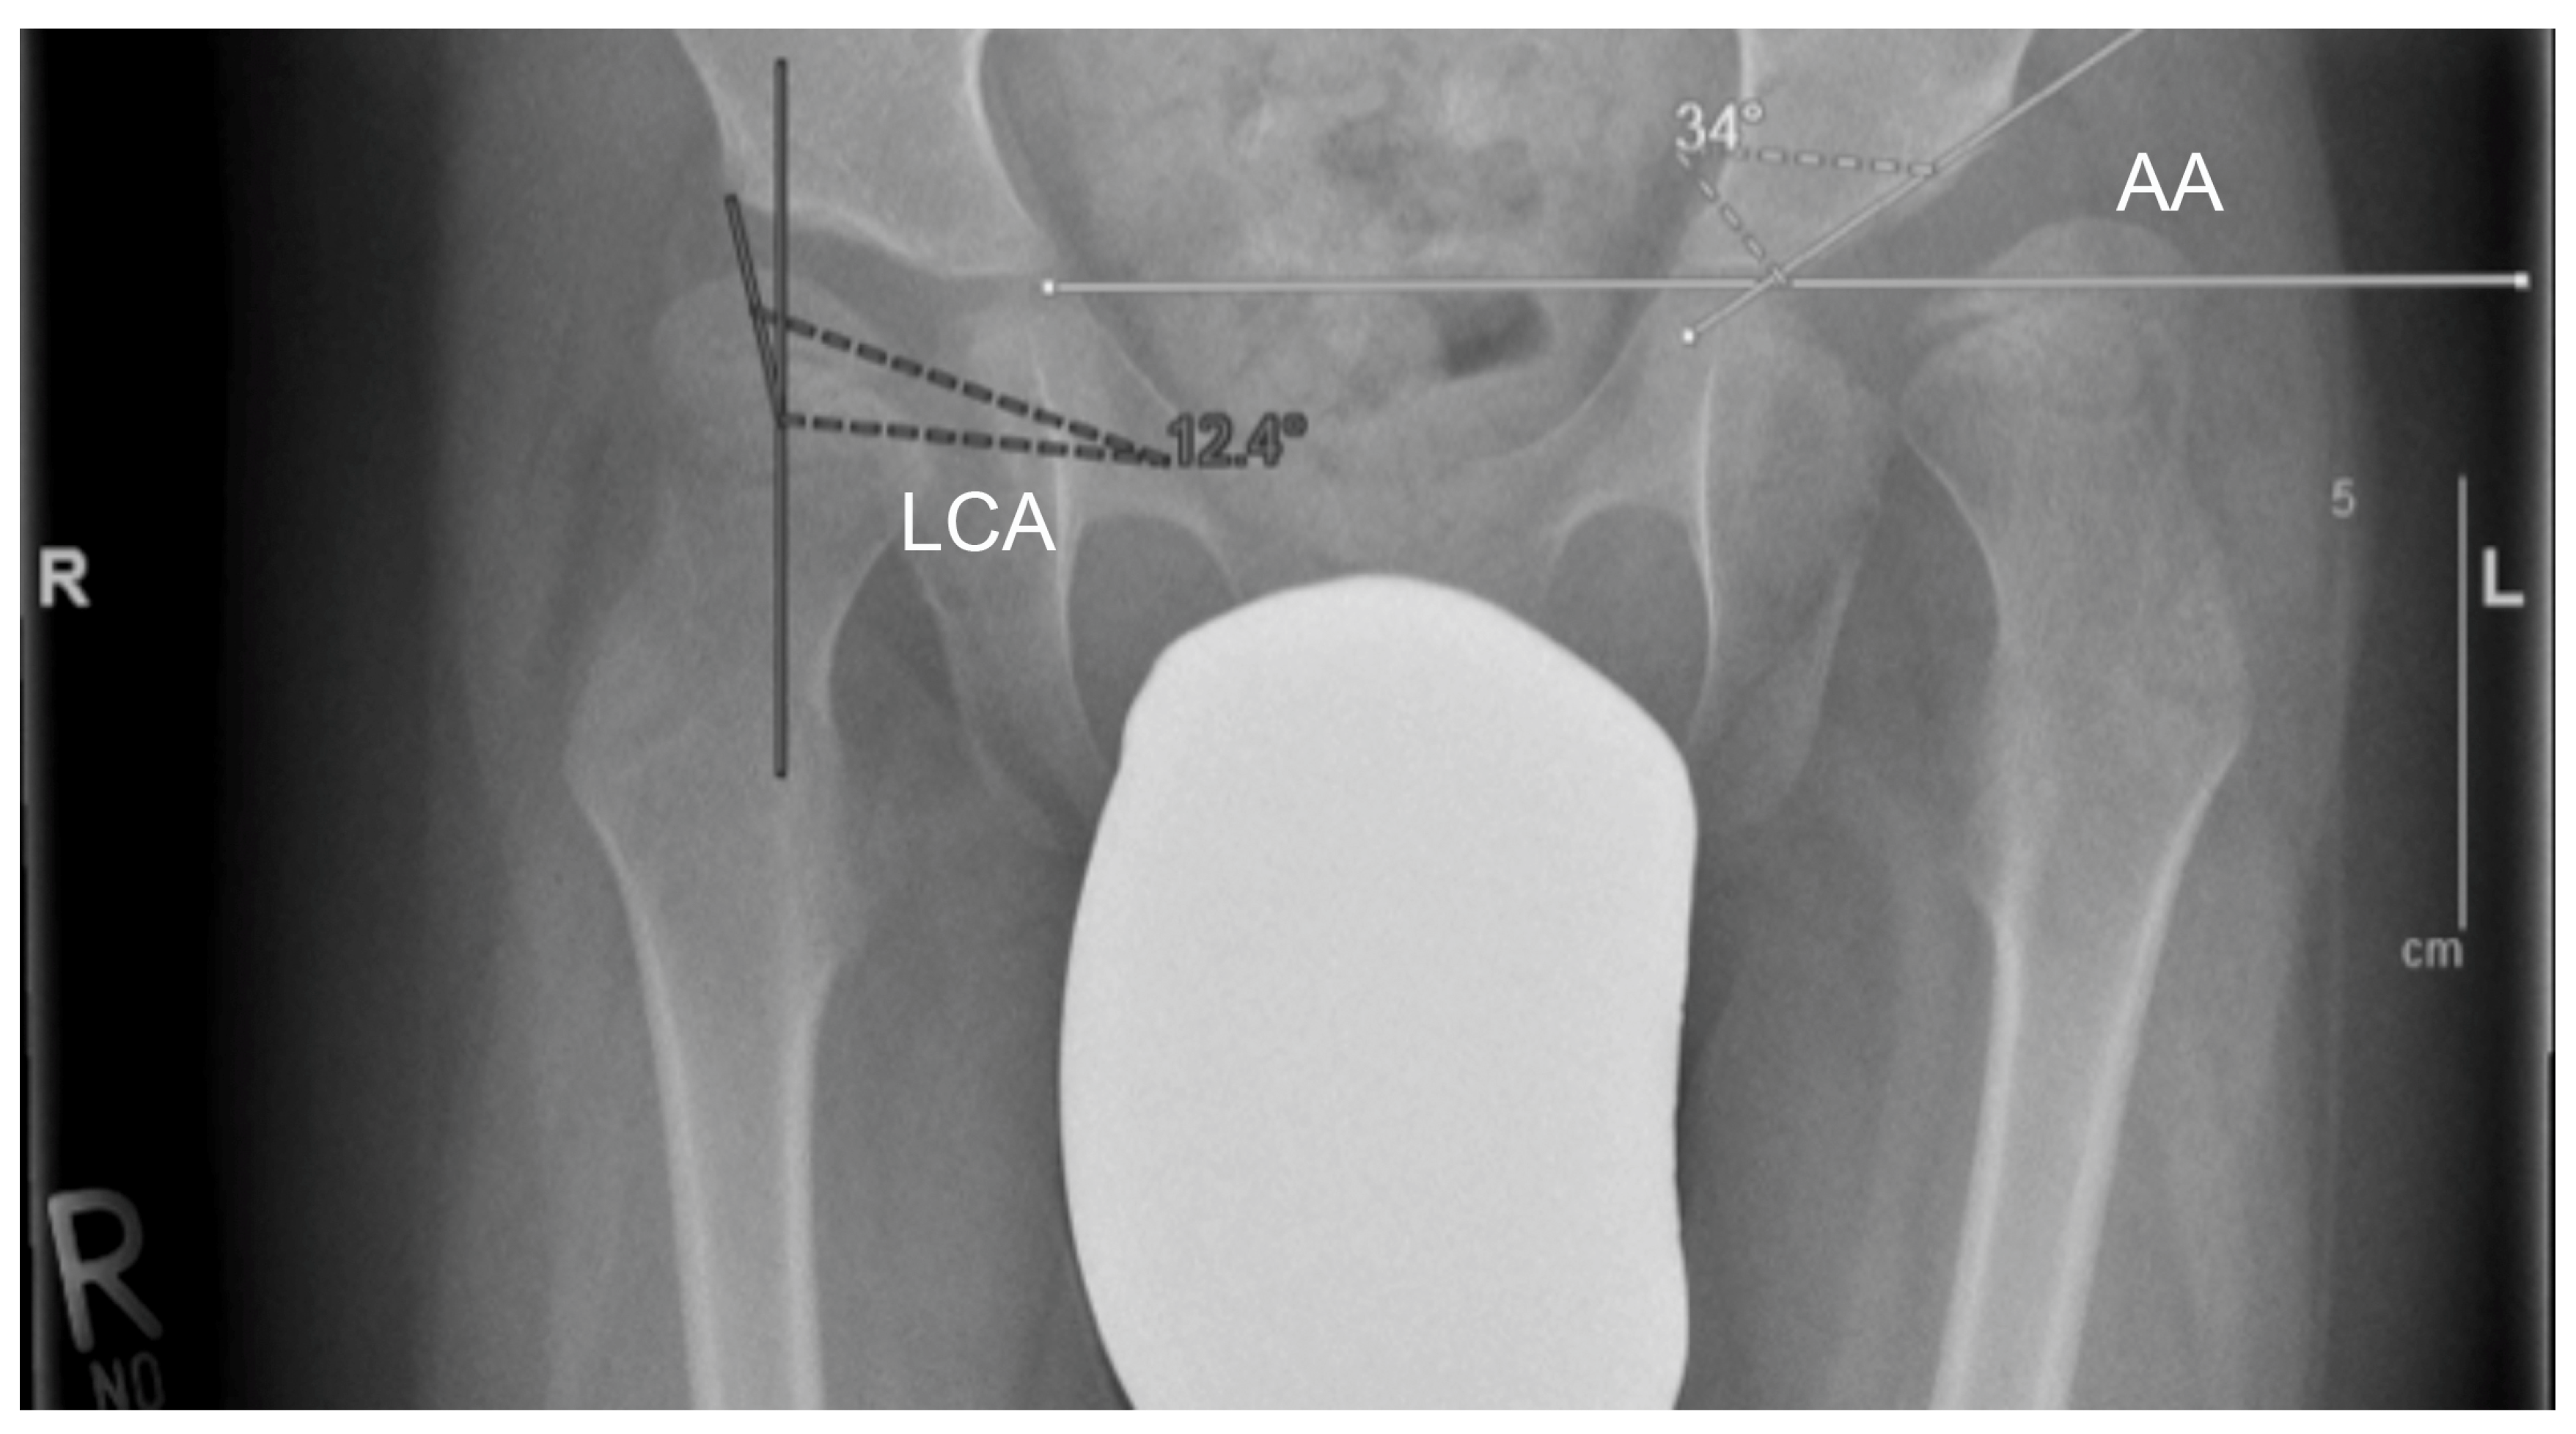

2.4. Radiological Assessment

| Acetabular Angle | Lateral Centre-Edge-Angle | ||||||

|---|---|---|---|---|---|---|---|

| Right | Left | Both | Right | Left | Both | ||

| Preoperative | Mean ± SD | 27.2 ± 5.4 | 28.9 ± 7.6 | 28.1 ± 6.7 | 11.2 ± 6.8 | 8.6 ± 6.4 | 9.9 ± 6.7 |

| Postoperative (1 week) | Mean ± SD | 14.0 ± 5.3 | 15.4 ± 4.9 | 14.7 ± 5.1 | 22.9 ± 7.0 | 20.4 ± 6.4 | 21.8 ± 6.8 |

| Postoperative (6 weeks) | Mean ± SD | 14.5 ± 5.5 | 15.4 ± 4.9 | 14.9 ± 5.2 | 22.2 ± 6.6 | 21.3 ± 6.2 | 21.8 ± 6.4 |

| Postoperative (1 year) | Mean ± SD | 14.8 ± 5.9 | 15.6 ± 5.6 | 15.2 ± 5.8 | 21.1 ± 6.7 | 20.5 ± 7.3 | 20.8 ± 6.9 |